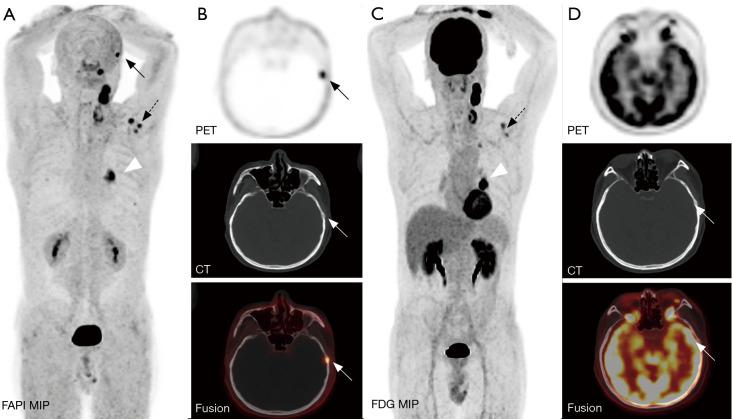

Bone metastases of lung cancer typically indicate disease progression and poor prognosis. Early and accurate detection is crucial for staging, treatment planning, and prognostic evaluation. This study aimed to compare the diagnostic value of gallium 68-labeled fibroblast-activation protein inhibitor-04 ([Ga]Ga-FAPI-04) and fluorine 18-labeled fluorodeoxyglucose ([F]FDG) positron-emission tomography/computed tomography (PET/CT) imaging in detecting bone metastases in lung cancer.

A retrospective analysis was conducted on patients with pathologically confirmed lung cancer and clinically suspected bone metastases. These patients underwent both [Ga]Ga-FAPI-04 and [F]FDG PET/CT imaging. Initially, all patient images were visually evaluated, and the diagnostic efficacy of the two imaging methods was compared at both the patient and lesion levels for detecting bone metastases from lung cancer. Additionally, a semi-quantitative analysis was performed to compare the optimal maximum standardized uptake value (SUVmax) threshold and diagnostic efficacy of the two examinations for diagnosing benign and malignant bone lesions.

A total of 25 lung cancer patients were included in the study, with nine confirmed cases and 133 lesions of bone metastases. At the patient level, there were no statistically significant differences in the detection rate, sensitivity, specificity, positive predictive value, negative predictive value, or accuracy between [Ga]Ga-FAPI-04 and [F]FDG PET/CT for identifying patients with bone metastases (P>0.05). At the lesion level, the detection rate, sensitivity, negative predictive value, and accuracy of [Ga]Ga-FAPI-04 PET/CT for detecting bone metastases were higher than those of [F]FDG PET/CT (81.37% 57.14%, 98.50% 69.17%, 88.24% 34.92%, 90.68% 70.81%), with statistically significant differences (P<0.01). The SUVmax of malignant bone lesions on both [Ga]Ga-FAPI-04 and [F]FDG PET/CT was significantly higher than those of benign bone lesions, with statistically significant differences (P<0.05). Moreover, the SUVmax of benign and malignant bone lesions on [Ga]Ga-FAPI-04 PET/CT was significantly higher than those on [F]FDG PET/CT, with statistically significant differences (P<0.01). In [Ga]Ga-FAPI-04 and [F]FDG PET/CT imaging, the area under the curves (AUCs) of SUVmax for diagnosing bone metastases were 0.856 and 0.724, respectively, with statistically significant differences (P<0.05); the optimal diagnostic thresholds were 5.38 and 3.77, respectively. The sensitivity, negative predictive value, and accuracy of SUVmax based on [Ga]Ga-FAPI-04 PET/CT for diagnosing lung cancer bone metastases were higher than those based on [F]FDG PET/CT (80.45% 65.26%, 46.49% 23.26%, 81.25% 67.29%), with statistically significant differences (P<0.05).

Compared to [F]FDG PET/CT, [Ga]Ga-FAPI-04 PET/CT significantly improves the detection rate of lung cancer bone metastases at the lesion level. Additionally, [Ga]Ga-FAPI-04 PET/CT offers superior image contrast and higher SUVmax, which also contribute to improving the accuracy of lung cancer bone metastasis diagnosis. This allows for more accurate staging of patients, enabling precise individualized treatment and improving patient prognosis.